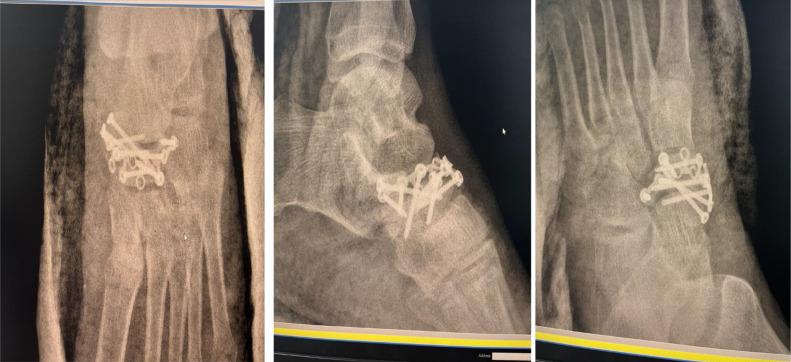

Navicular fractures, although rare, can cause significant midfoot pain and dysfunction. This case report discusses the presentation, diagnosis, and surgical management of an acute navicular fracture with dorsal talo-navicular dislocation in a 30-year-old male. The patient, with no significant medical history, sustained the injury after falling from a height of approximately 3 meters. Initial clinical examination revealed midfoot swelling, ecchymosis, and tenderness, with imaging confirming the fracture and dislocation. The patient underwent open reduction and internal fixation (ORIF) of the fracture. The surgical approach included the use of Schanz pins and a locking compression plate (LCP) for fixation. Postoperative management involved a period of immobilization, with gradual weight-bearing allowed at 8 weeks. The patient showed no signs of complications during follow-up and achieved a favorable recovery. This case highlights the importance of early diagnosis, prompt surgical intervention, and appropriate follow-up in preventing long-term complications such as nonunion and osteoarthritis.

舟骨骨折虽罕见,但可导致严重的中足疼痛和功能障碍。本病例报告讨论了一名30岁男性急性舟骨骨折伴距舟背侧脱位的临床表现、诊断及手术治疗。该患者无重大病史,从约3米高处坠落受伤。初始临床检查发现中足肿胀、瘀斑和压痛,影像学检查证实骨折和脱位。患者接受了骨折切开复位内固定术(ORIF)。手术方法包括使用斯氏针和锁定加压钢板(LCP)进行固定。术后处理包括一段时间的固定,8周时允许逐渐负重。随访期间患者未出现并发症迹象,恢复良好。本病例强调了早期诊断、及时手术干预及适当随访在预防骨不连和骨关节炎等长期并发症方面的重要性。